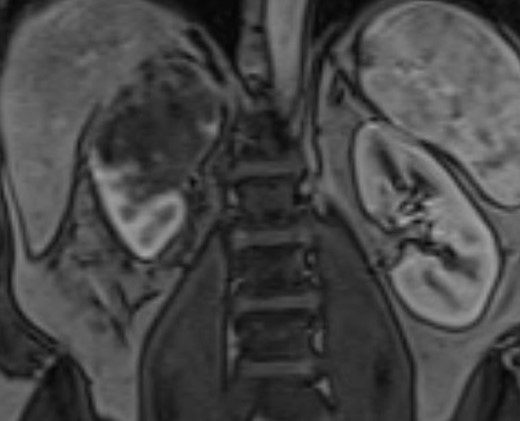

A 51-year-old white male with BMI of 29.7 was referred for gross hematuria. Renal ultrasound identified right hydronephrosis and ureteroscopy demonstrated high grade T2 urothelial carcinoma. CT and MR imaging revealed an 8 cm upper pole infiltrative tumor which obliterated the right renal vein without caval thrombus (Figs 1 and 2). There was no evidence of metastasis on CT chest. The preoperative estimated glomerular filtration rate was 71 ml/min/1.73 m2. Multidisciplinary review was undertaken and a radical nephroureterectomy and lymph node excision was recommended without neoadjuvant chemotherapy.

Coronal MRI of the abdomen/pelvis demonstrating the 8 cm right upper pole renal mass.